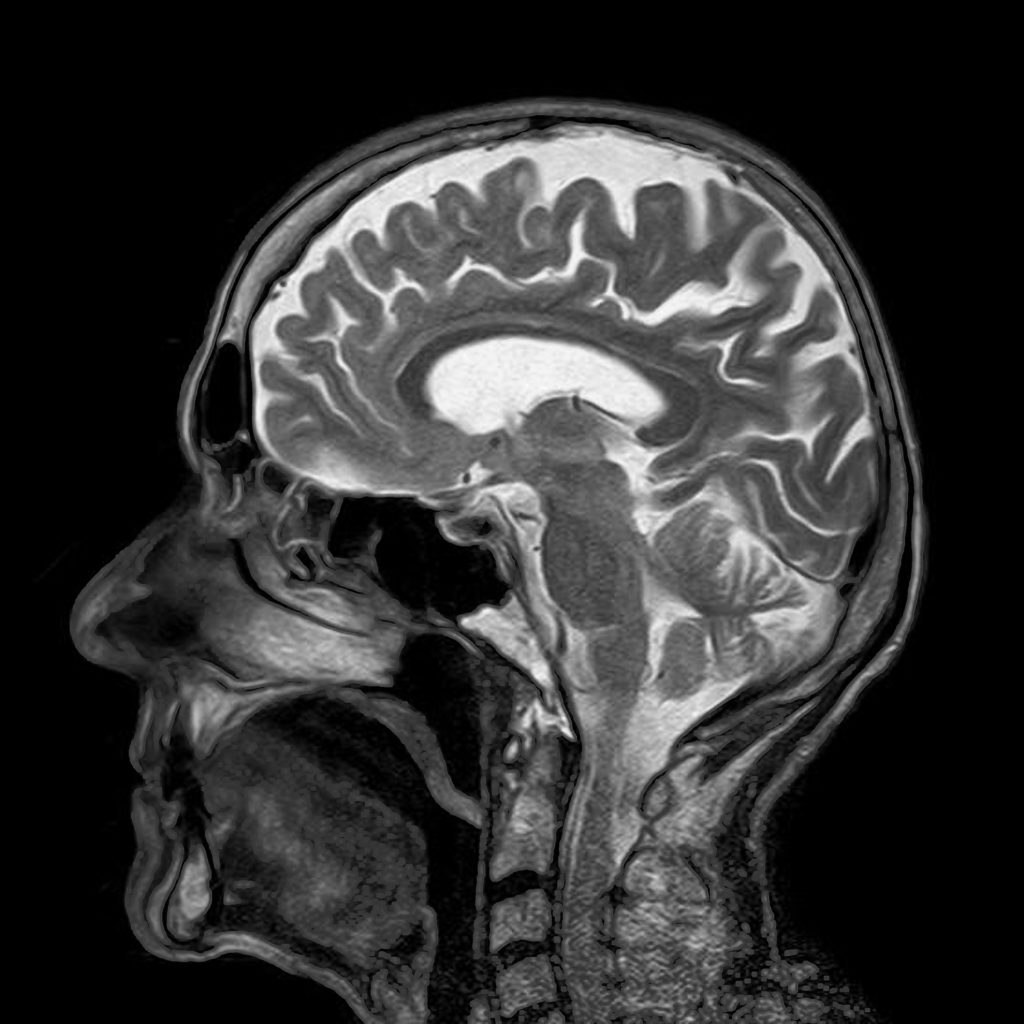

When Brain Imaging is Needed to Diagnose Headache

Can You Get A Headache From An Mri . mri can't diagnose migraines or headaches but it can rule out other medical conditions. if you have episodes of migraine, you know that they’re more than severe headache pain. many providers would consider ordering brain imaging studies, such as ct scans and mris, to help them diagnose worsening. an mri of the brain can be used to evaluate many symptoms which may be caused by abnormalities in the central nervous system. In the vast majority of cases, mri is essentially normal. a healthcare provider will use their judgment to determine if you should have an mri with contrast or a regular mri. These include headache, seizures, sleep disorders, mental confusion, weakness, numbness, or dizziness. This common neurological condition affects more. Getting an mri with contrast is generally safe but rarely may cause side effects such as nausea and vomiting.